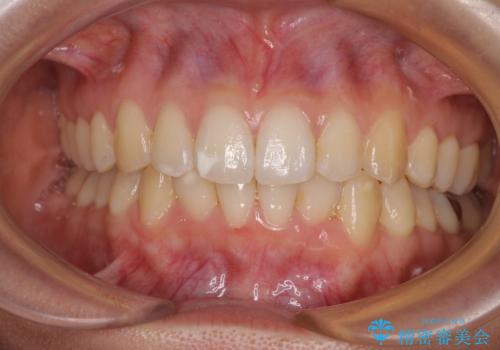

- 上下のクロスバイトと前歯のデコボコを気にして来院された患者様です。

インビザラインを用い、IPR(歯と歯の間を削る)と歯列全体を拡大させることで、歯並びを整えていくこととしました。

下の歯が隠れてしまうほどでしたが、深い咬み合わせも改善され、顎への負担も軽減されました。